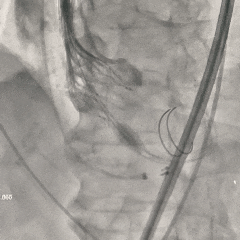

第二次释放至全展开位

瓣膜释放过程中猪尾导管上移,瓣架轻微下移至瓣上2mm左右

全展开位造影评估

瓣架形态可,无窦侧深度约瓣上2mm,小弯侧深度接近零位,瓣架整体贴靠左窦侧,右冠显影正常,左冠显影尚可,可见少量瓣周漏

冠脉风险充分评估

调整至左头位再次造影,可见左、右冠显影可

使用左冠导管造影,可见左冠显影可

再次调整体位重新造影,可见右冠灌注正常。决定准备瓣膜脱钩释放